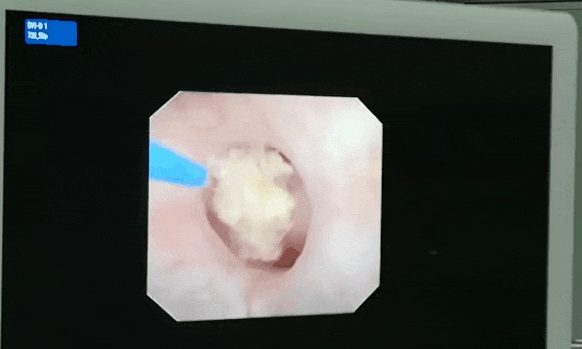

▲智能控压清石系统联合输尿管软镜钬激光碎石取石术

术中,无需打孔,经尿道 — 膀胱 — 输尿管,借助输尿管软镜,利用激光顺利粉碎结石,再通过软镜配合负压吸引系统吸出,彻底清除碎石,患者术后康复情况良好,获得患者们一致好评。